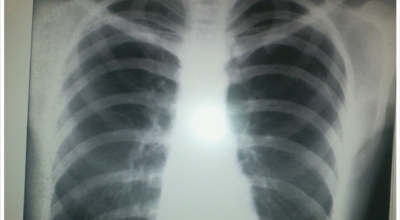

일반인이 근육의 통증과 금이 간 경우의 차이는 거의 판별하기 힘들게 됩니다. 갈비뼈라고 하는 부분이 눈에 보이도록 붓는 것도 아니고, 멍이 들어서 아픈것도 아니기 때문이예요. 가장 정확하게 판별하는 방법은 엑스레이를 찍는 방법이예요.